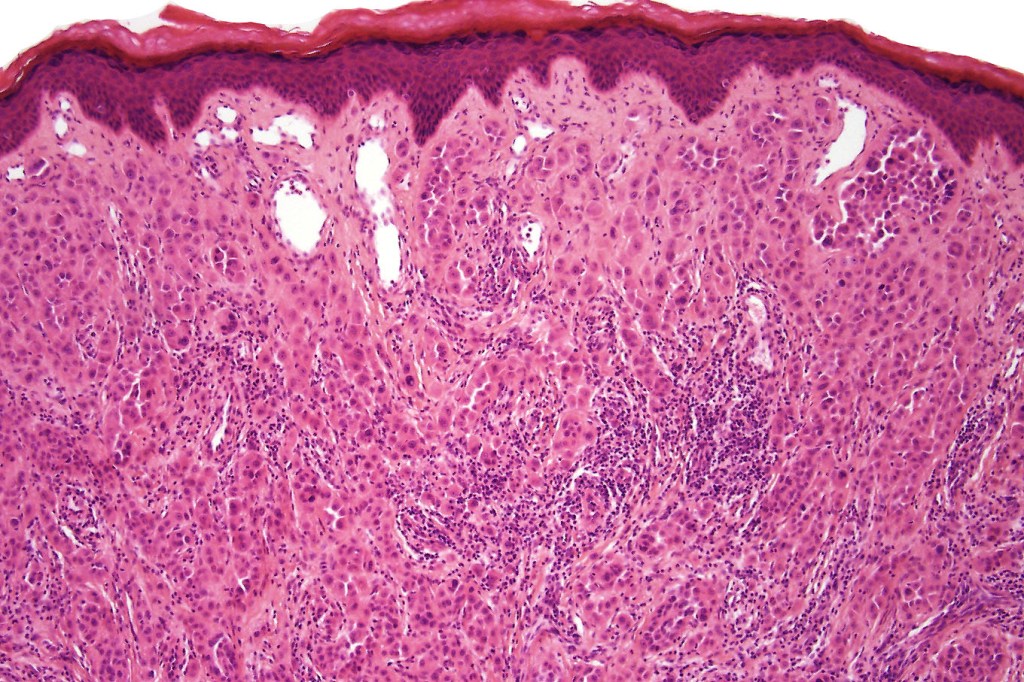

•Sharply circumscribed (begins and ends with a nest), symmetrical dome-shaped lesion. Symmetry is both horizontal and vertical (see image below)

•Wedge-shaped with the base uppermost or sometimes plaque-shaped silhouette

•Hyperkeratosis & acanthosis, sometimes very marked

•Superficial vascular ectasia very frequently present

•Junctional nests often vertically orientated, dyscohesive with a surrounding retraction artifact

•Pleomorphism is almost invariable but affects all of the population to the same extent i.e., the cells & nuclei all look very much the same

•Kamino bodies (often multiple) are a characteristic feature

•Lymphocytic infiltration at the base of the lesion